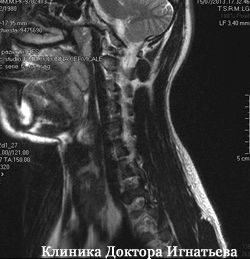

Лікар проводить диференціальну діагностику для встановлення справжньої причини недуги. Тому, виключається можливість розвитку таких захворювань, як остеохондроз, остеопороз шийного відділу хребта, грижі міжхребцевого диска. сколіоз, кіфоз, ракові пухлини, удари і травми.

Перед лікуванням пацієнт проходить обстеження: здає аналізи крові, сечі, проходить рентгенографію, МРТ. У «Клініці доктора Ігнатьєва» г. Киев практикується індивідуальний підхід до кожного пацієнта. Мануальний терапевт поставить діагноз і призначить комплексне лікування.